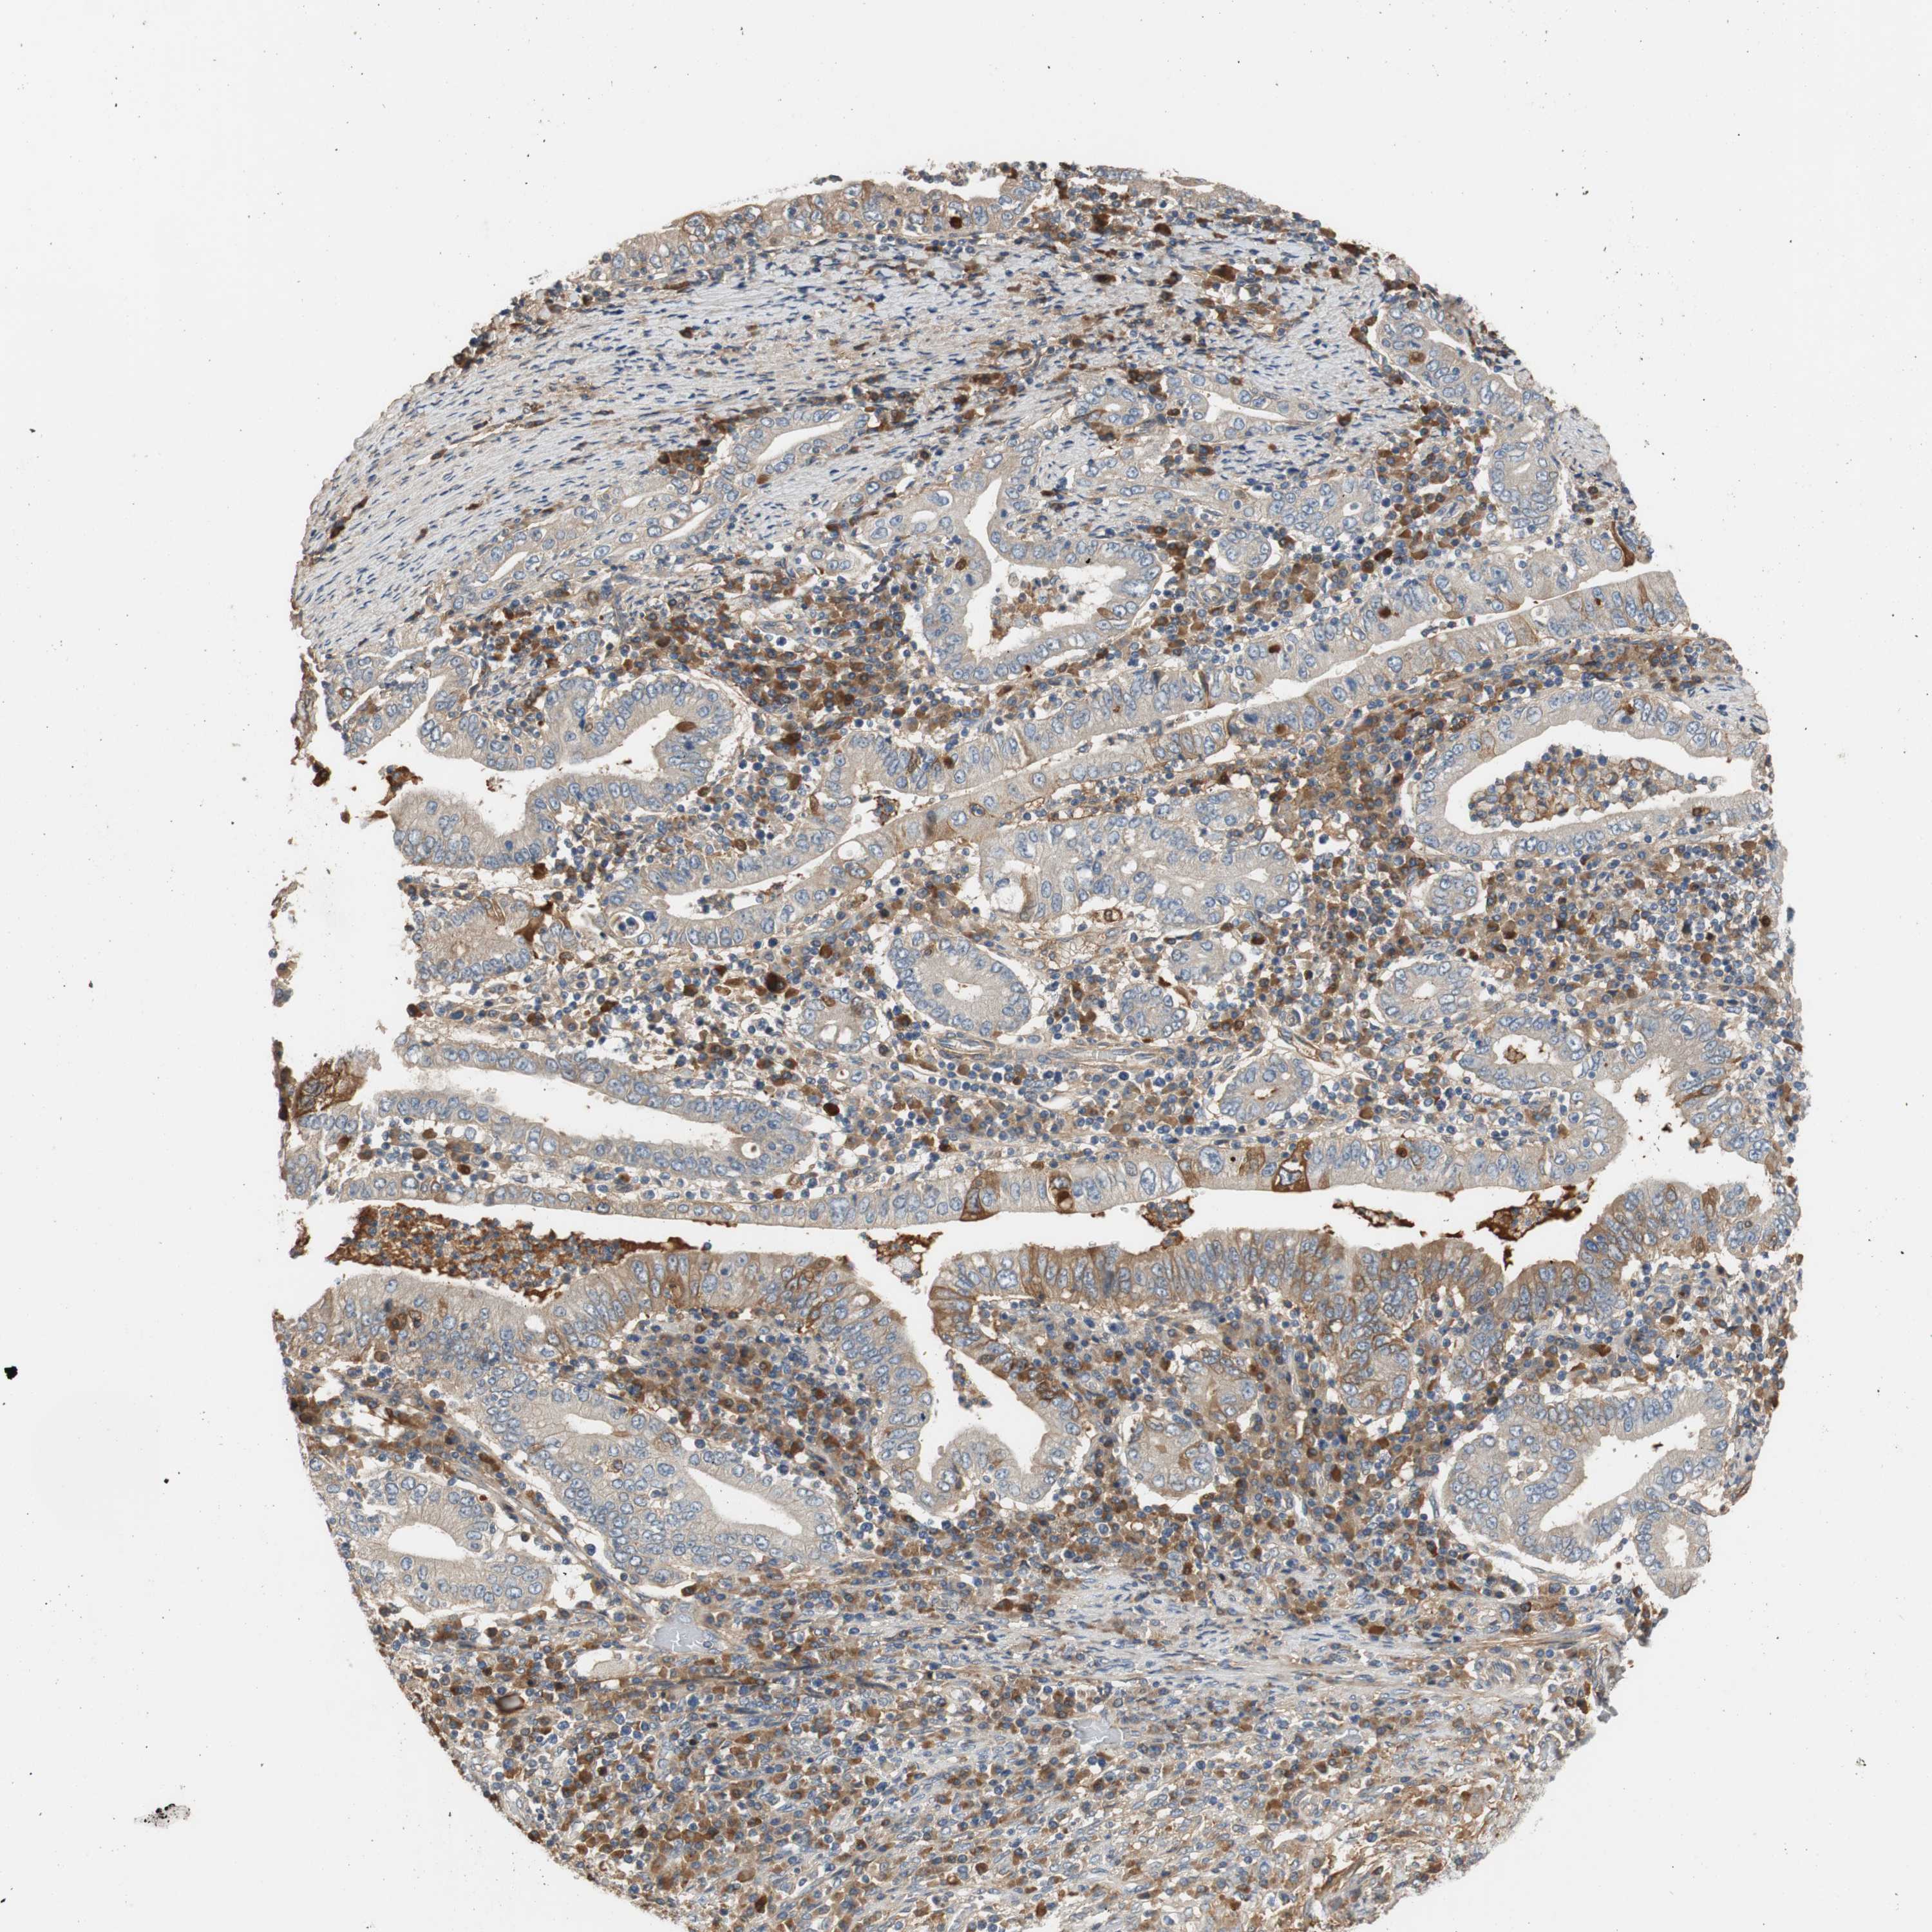

STOMACH CANCER - Protein expressioni

A mouse-over function shows sample information and annotation data. Click on an image to view it in a full screen mode. Samples can be filtered based on level of antibody staining by selecting one or several of the following categories: high, medium, low and not detected. The assay and annotation is described here.

Note that samples used for immunohistochemistry by the Human Protein Atlas do not correspond to samples in the TCGA dataset.

Antibody stainingi

Antibody staining in the annotated cell types in the current human tissue is reported as not detected, low, medium, or high, based on conventional immunohistochemistry profiling in selected tissues. This score is based on the combination of the staining intensity and fraction of stained cells.

Each image is clickable and will lead to virtual microscopy that enables deeper exploration of all samples and also displays staining intensity scores, fraction scores and subcellular localization as well as patient and tissue information for each sample.

HPA046356

Staining

High

Intensity

Strong

>75%

Nuclear

Adenocarcinoma, NOS